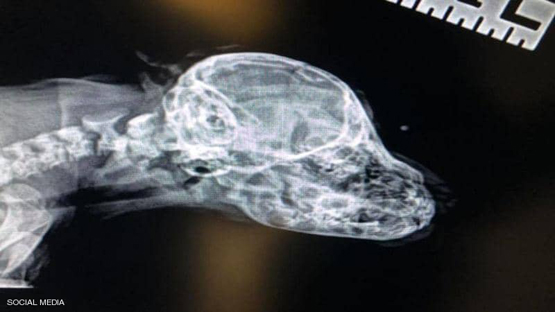

وبعد إخضاعه للأشعة، وجد الأطباء أن الذيل غير مرتبط بأي شيء آخر داخل جسم الحيوان، إلا أن الجمعية الخيرية قالت إن ذيل ناروهال يجعله "أروع كلب على الإطلاق".